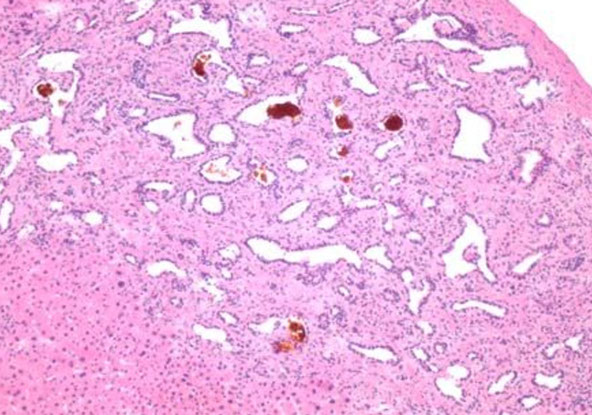

Peliosis Hepatis

- localized areas of sinusoidal dilation of variably-sized cavities, causing blood-filled pools / lakes

- liver usually enlarged and diffusely involved, and can affect spleen

- MCC are chronic debilitating dz's (TB, cancer), drugs, bacillary peliosis assoc c Bartonella henselae

- vascular pools can have liquid blood, though can see early thrombosis and organization at edges

- no cirrhosis usually seen in background liver